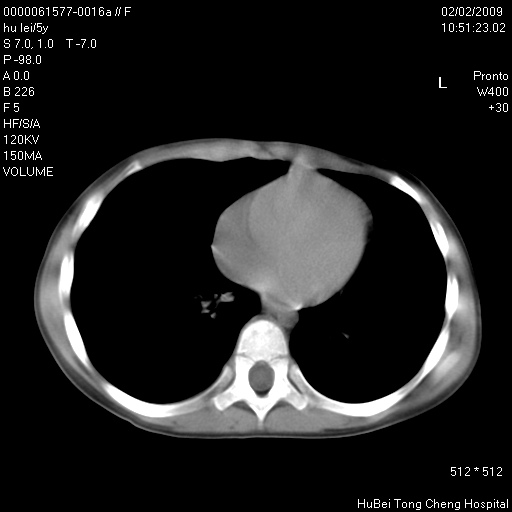

标题: PED1732:M5Y,右肺囊性占位!

患者:男,5。无明显不适,拍胸片考虑右肺囊肿。

行ct扫描,图象如下:

考虑支气管囊肿或皮样囊肿

考虑先天性巨大支气管肺囊肿

考虑右肺支气管源性肺囊肿